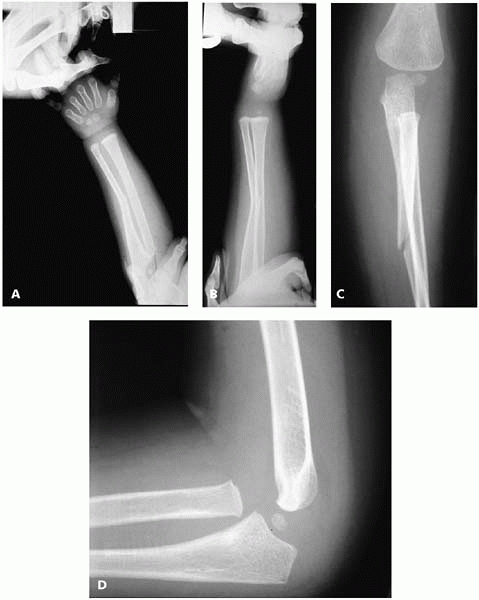

be “ruler straight”13 (Fig. 7-9).

A line drawn down the shaft of the radius should point to the center of

the capitellum. Be sure to assess this after initial reduction and at

each follow-up, as late dislocation of the radial head has been

![]() |

|

▪ FIGURE 7-8

Four types of Monteggia fractures, as described by Bado. (Reprinted with permission from Wilkins KE, O’Brien ET. Fractures of the Distal Radius and Ulna. In Rockwood CA Jr., Wilkins KE, Beaty JH, eds. Fractures in Children, 4th ed. Philadelphia: Lippincott-Raven, 451-651.) |

▪ FIGURE 7-9

The ulna should be “ruler straight.” This radial head dislocation is associated with plastic deformation of the ulna (anterior bowing). Many of the children who present with “isolated” or “congenital” radial head dislocations actually had a Monteggia fracture of equivalent. (Reprinted with permission from Price CT, Flynn JF. Management of fractures. In Morrissy RT, Weinstein SL, eds. Lovell and Winter’s Pediatric Orthopaedics, 6th ed. Philadelphia, Lippincott Williams & Wilkins, 2006.) |